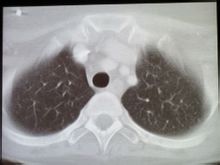

病理診斷圖BL是一種高度侵襲性的淋巴瘤,常發生在結外或表現為急性白血病形式,腫瘤由細胞單一,中等大小的B細胞組成,胞質嗜鹼性、核分裂象多見。常有myc基因的異位,部分病例有EBV感染。

伯基特淋巴瘤病變部位表現為腫塊,瘤組織呈魚肉狀、伴出血壞死。相鄰器官受壓和浸潤。淋巴結受累少見,但淋巴結周圍可被腫瘤包圍。細胞單一、中等大小,瀰漫浸潤。固定後細胞有時呈鋪路石或鑲嵌樣排列。核圓形、染色質粗,副染色質相對清晰,核中等大小、居中,嗜鹼性。胞質深嗜鹼、常伴有脂質空泡。印片中這些細胞的細微結構更容易觀察。腫瘤增殖率很高(核分裂多見),並且細胞自發性死亡率高(凋亡)。“滿天星”現象常見,這是巨噬細胞吞噬凋亡的腫瘤細胞所致。腫瘤細胞核的大小近似於“滿天星”中的組織細胞核。